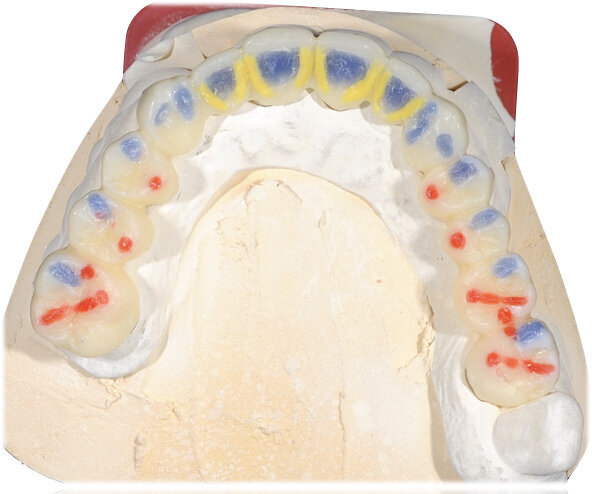

Il fresato ottenuto è poi riportato su articolatore Reference SL – già opportunamente programmato – e viene dall’Odontotecnico competente più precisamente funzionalizzato secondo i criteri della programmazione funzionale sequenziale, evidenziando con cere colorate i rapporti di centrica, le funzioni di mediotrusiva e protrusiva e le protezioni retrusive. I monconi sfilabili consentono la modellazione della sequenzialità mediotrusiva con la guida incisale indicata dalla registrazione axiografica (blu) (Figg. 34-37). La ceratura sequenziale è ora scansita con Sirona InEos X5 su Exocad, ed il modellato viene ricontrollato al CAD per spessori, connessioni e morfologia, e nella regolazione degli offsets per la ripreparazione dei monconi, ed è inviato al CAM per la fresatura dei II provvisori in Bredent breCAM.multicom, un PMMA con microriempitivo ceramico ad alta stabilità, su Dental Plus 5 Axis Milling Machine. La rifinitura dei monconi è seguita da ribasatura dei II provvisori in TRP - previo isolamento di tutte le superfici funzionali - e gli stessi sono poi rifiniti e lucidati. I soli elementi 3.3, 4.2 e 4.3 sono rimodellati in regione incisale con addictions in composito, secondo la morfologia studiata in ceratura. La consegna conferma la buona integrazione dei manufatti dal punto di vista estetico, occlusale, articolare e neuromuscolare, con controllo occlusale conforme al progetto (Figg. 38-42).

Il paziente utilizza questi secondi provvisori per otto settimane, durante le quali conferma la buona integrazione dei restauri e la soddisfacente funzione occlusale. Ciò è verificato con l’esecuzione di una nuova axiografia elettronica che già a due settimane dalla consegna evidenzia una buona risposta muscolare al nuovo design occlusale ed alla nuova postura mandibolare in TRP (Figg. 43-46). Provvediamo infine alle impronte per la costruzione dei manufatti definitivi in Zirconia-ceramica. I modelli sono scansiti in laboratorio con inEos X5 (Dentsply Sirona) su exocad (Figg. 47-49), ed una seconda scansione viene eseguita con i provvisori del Paziente posizionati sui modelli (Figg. 50-52). Il CAD consente di eseguire un matching fra le due scansioni, per cui i secondi provvisori utilizzati in TRP, con funzione occlusale sequenziale già completamente programmata, sono utilizzati per definire le morfologie dentali definitive di tutti gli elementi da restaurare (Figg. 53, 54) secondo il rapporto intermascellare definito (Figg. 55-58). Si esegue quindi fresatura al CAM della protesi definitiva in zirconia (Figg. 59, 60), la stratificazione e finitura ed infine la consegna al Paziente con cementazione in Panavia V5 (Figg. 61-65).